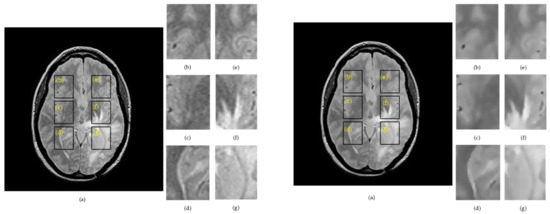

Figure 2 and Figure 3 show examples for the implementation of SSIMs and skeletonization for right– left correspondents for a raw image containing Rician noise (left panel) and a filtered image by the anisotropic diffusion filter (right panel).

Figure 2. Example of extracting regions of interes ROIs in proton density PD image for a patient with glioma, where: Left side: (a) raw image. Right side: (a) denoised image. (b) ROI 1L; (c) ROI 2L; (d) ROI 3L; (e) ROI 1R; (f) ROI 2R; and (g) ROI 3R.